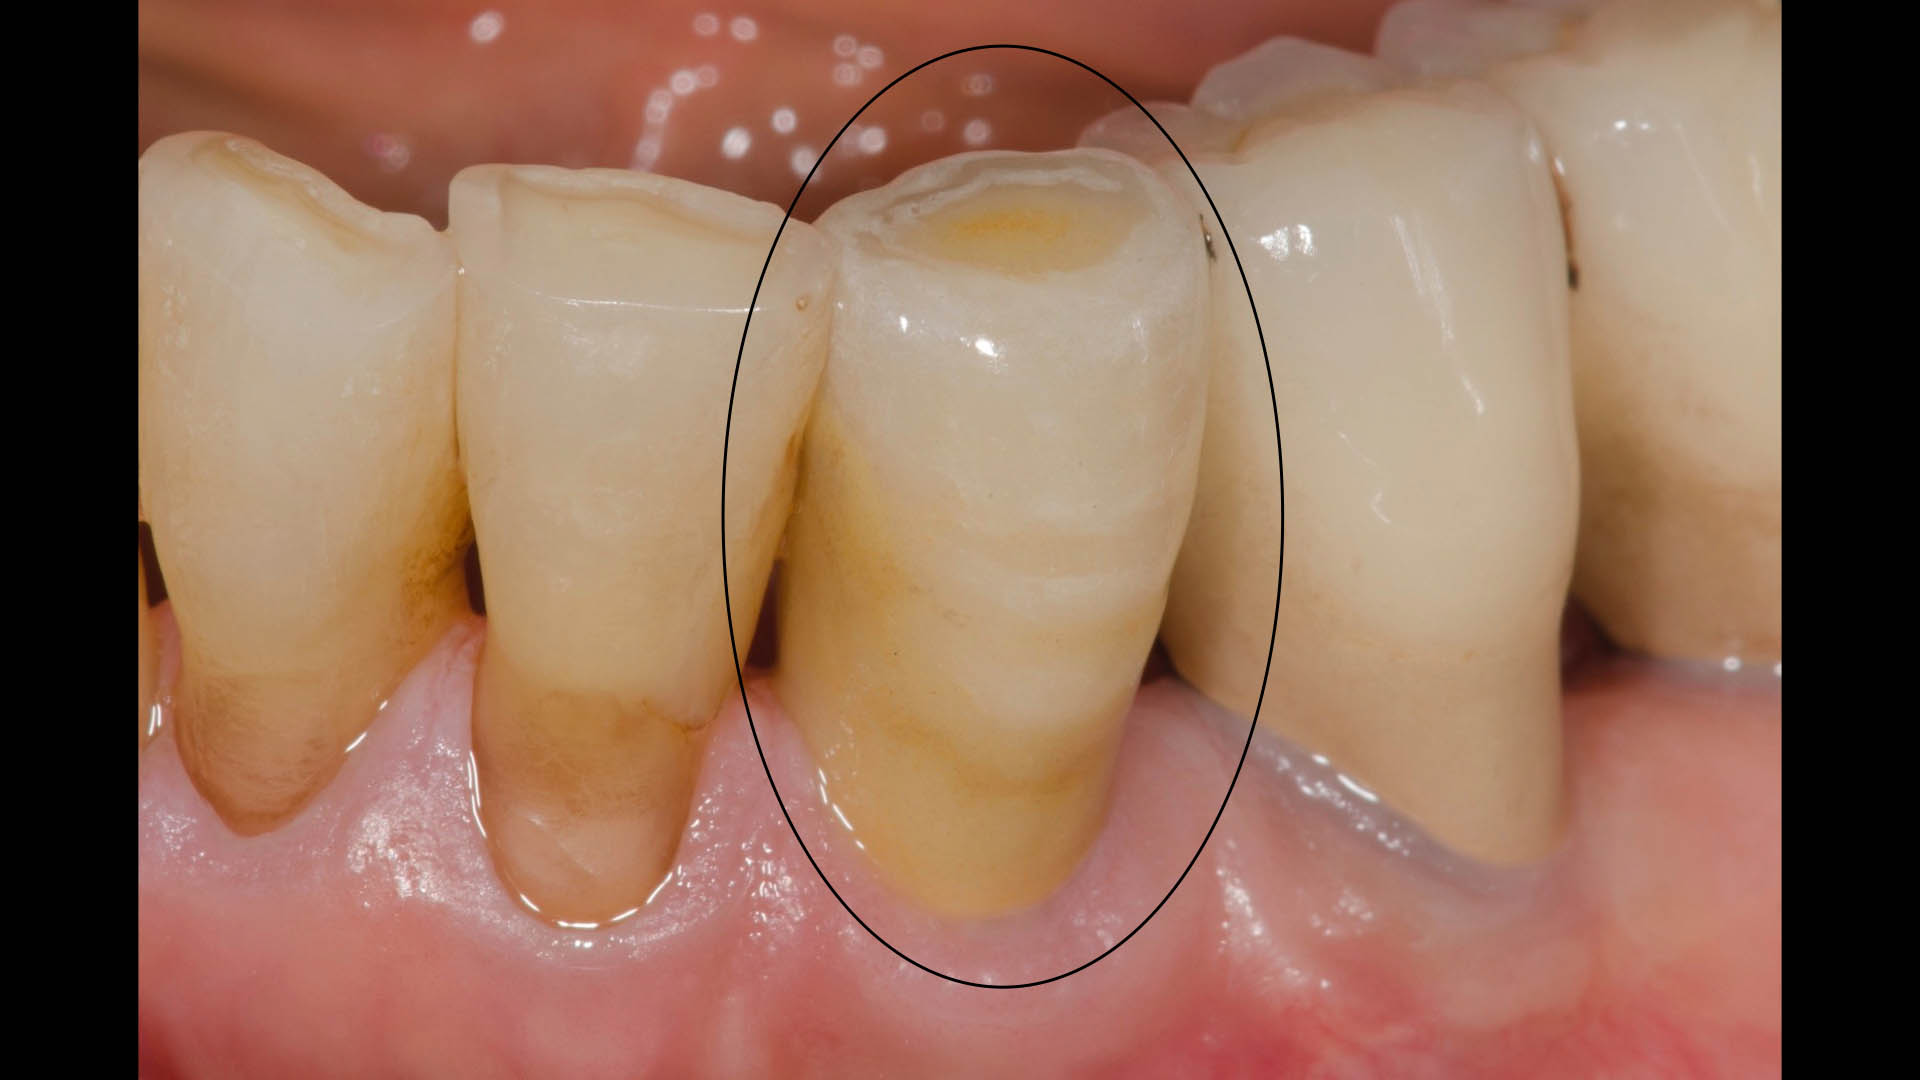

Take a glimpse into the magic of Coral Gables Dentistry through our before and after pictures. See firsthand the incredible smile makeover transformations that have brought confidence and joy to our patients.